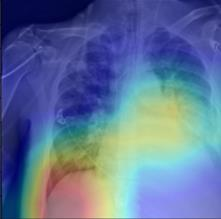

Thoracic disease detection from chest radiographs using deep learning methods has been an active area of research in the last decade. Most previous methods attempt to focus on the diseased organs of the image by identifying spatial regions responsible for significant contributions to the model's prediction. In contrast, expert radiologists first locate the prominent anatomical structures before determining if those regions are anomalous. Therefore, integrating anatomical knowledge within deep learning models could bring substantial improvement in automatic disease classification. This work proposes an anatomy-aware attention-based architecture named Anatomy X-Net, that prioritizes the spatial features guided by the pre-identified anatomy regions. We leverage a semi-supervised learning method using the JSRT dataset containing organ-level annotation to obtain the anatomical segmentation masks (for lungs and heart) for the NIH and CheXpert datasets. The proposed Anatomy X-Net uses the pre-trained DenseNet-121 as the backbone network with two corresponding structured modules, the Anatomy Aware Attention (AAA) and Probabilistic Weighted Average Pooling (PWAP), in a cohesive framework for anatomical attention learning. Our proposed method sets new state-of-the-art performance on the official NIH test set with an AUC score of 0.8439, proving the efficacy of utilizing the anatomy segmentation knowledge to improve the thoracic disease classification. Furthermore, the Anatomy X-Net yields an averaged AUC of 0.9020 on the Stanford CheXpert dataset, improving on existing methods that demonstrate the generalizability of the proposed framework.